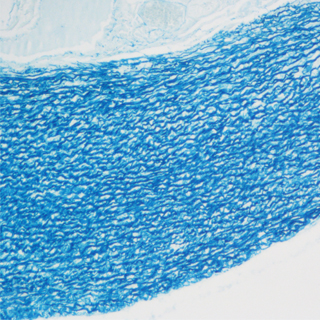

實驗結果:

脂滴呈橘紅色至鮮紅色:細胞核呈深藍色。